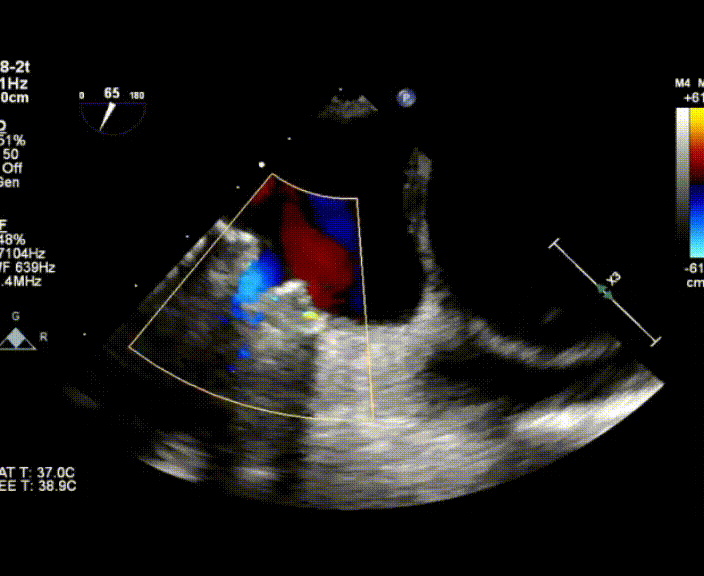

超聲心動圖提示:右心增大,右室肥厚,左室測值偏小,房間隔中份探及修補術后回聲,房水平未見殘余分流,三尖瓣重度反流,重度肺動脈高壓,中度肺動脈瓣反流,左室收縮功能測值正常,右室收縮功能減低 。

術中首先在局麻下穿刺股動脈、股靜脈,完成心導管檢查評估后轉為全麻,在食道超聲引導下穿刺房間隔,穿刺成功后將加硬導絲送入左上肺靜脈建立軌道,根據(jù)患者病情行球囊預擴張后植入6mm孔徑房間隔造孔支架,經(jīng)透視及食道超聲評估支架左右盤展開良好,夾持于房間隔兩側,固定穩(wěn)定、位置良好,食道彩超顯示房水平右向左為主分流,分流孔直徑符合預期大小,心導管檢查評估達到預期效果,釋放造孔支架。術后12h患者下床活動,恢復順利,擬于近日完善術后評估后出院。

心房分流術是通過器械制造穩(wěn)定可控的心房間分流,適應證包括藥物治療效果不佳的左心衰或肺動脈高壓右心衰。本例患者為肺動脈高壓右心衰,術中成功放置MicroFlux®造孔支架在房間隔理想位置上,創(chuàng)造穩(wěn)定可控的心房間分流(此例患者以右向左分流為主),在不顯著增加左心負擔的情況下,有效降低患者右心房壓力、緩解體循環(huán)淤血,增加左心輸出量,改善患者癥狀、活動耐力和生存質量。同時,國內外也已經(jīng)開展多項房間隔造孔支架在射血分數(shù)保留、射血分數(shù)中間值和射血分數(shù)降低的左心衰患者中的臨床研究,結果顯示對于經(jīng)過充分的規(guī)范化藥物治療后仍控制不佳的患者,心房分流術可改善患者的癥狀及生存質量?! ?/p>